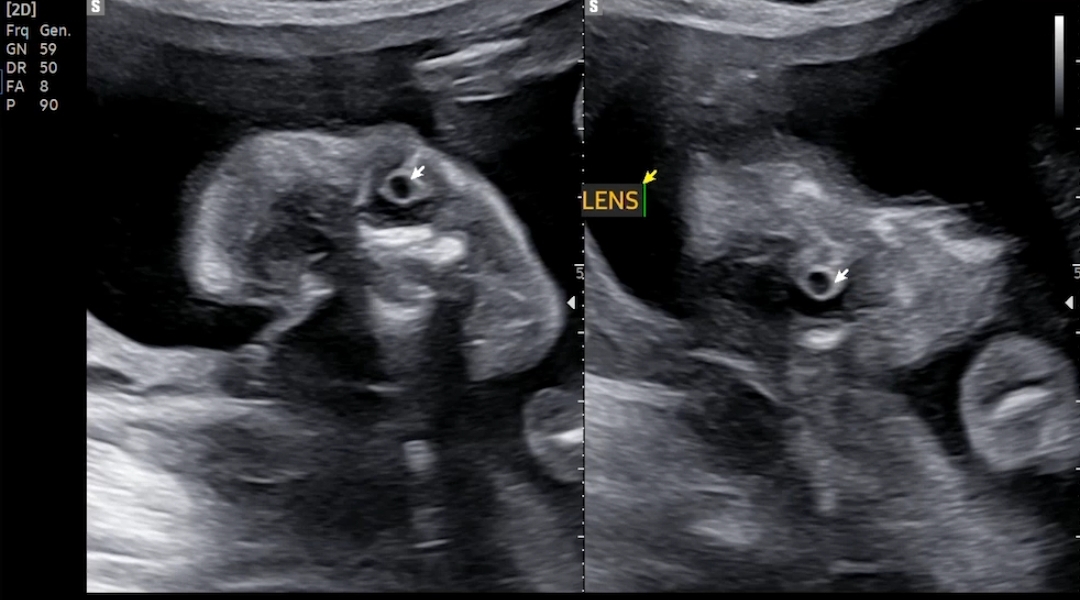

약간 흠칫한 눈동자..! ㅋㅋ 양쪽 눈 확인완료~

자세히 봐주셨던 콧구멍과 입술이구요. 혹시나 구순구개열 있는지 꼼꼼히 보는 과정이었는데, 다행히 갈라짐은 전혀 없었어요.